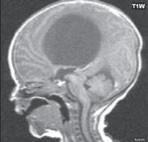

I.1.8 Dandy-Walkerova malformace (D-W variant, D-W komplex, D-W spektrum )

Zobrazení

D-W malformace je charakterizována hypoplazií vermis mozečku, rozšířením IV. mozkové komory, která se často cysticky vyklenuje dorzálně a může imitovat arachnoidální cystu, rozšířením zadní jámy lební a vysokým úponem tentoria s confluens sinum nad lambdovým švem. Okcipitální kost může být vlivem tlakových změn remodelována, existují i případy s porušením její kontinuity a encefalokélou. Hydrocefalus pozorujeme v 80 %, častá je přítomnost dysgeneze corpus callosum, schizencefalie.

D-W variant byl vyčleněn pro případy, kdy všechny základní příznaky nemusí být plně vyjádřeny nebo může některý zcela chybět. Bývá přítomna hypoplazie mozečku, což je dominantní příznak, IV. komora je obvykle rozšířena, někdy pozorujeme, že tvarem připomíná na axiální řezu „klíčovou dírku“, zadní jáma lební naopak rozšířena nebývá.

Obr. I.1.8a Dandy-Walkerova malformace, rozšířená IV komora (tvar klíčové dírky)

Obr. I.1.8b Dandy-Walkerova malformace, rozšířená IV komora široce komunikující s cisterna magna, hypotrofie mozečku (snímky zapůjčeny z archivu prim doc MUDr M Mechla, Ph D, MBA)

Obr. I.1.8c Dandy-Walkerova malformace, rozšířená IV komora široce komunikující s cisterna magna, hypotrofie mozečku (snímky zapůjčeny z archivu prim doc MUDr M Mechla, Ph D, MBA); stejný pacient jako na obr I 1 8b

Obr. I.1.8d Dandy-Walkerova malformace, rozšířená IV komora široce komunikující s cisterna magna, hypotrofie mozečku, vysoký úpon tentoria (šipka) (snímky zapůjčeny z archivu prim doc MUDr M Mechla, Ph D, MBA); stejný pacient jako na obr I 1 8b, c